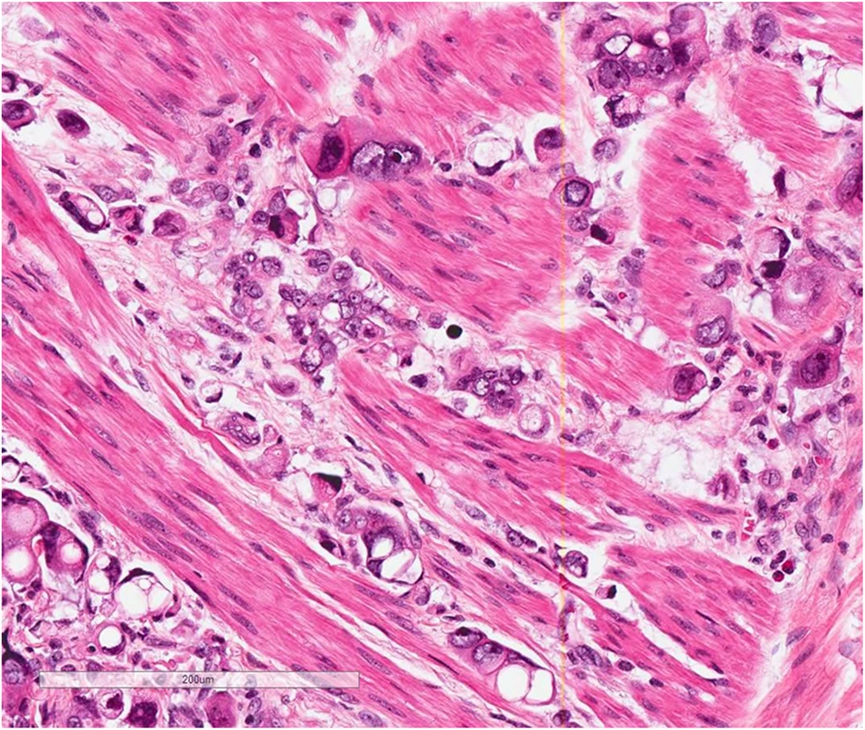

图3. PUC的瘤细胞显示胞质内空泡,呈印戒细胞样,但不是真正的印戒细胞

PUC中大约有一半是纯粹的浆细胞样尿路上皮癌,但也可以伴发于经典的尿路上皮癌、肉瘤样尿路上皮癌、微乳头状尿路上皮癌,巢状尿路上皮癌和小细胞癌。细胞排列成条索状,列兵样,小巢状,实性成片,偶尔会呈现欺骗性的良性外观,从而误诊为炎症。间质可能呈黏液样外观,并可见胞质内空泡,但并不是真正的印戒细胞。在30%–43%的病例中存在血管浸润。在现在报道的病例中,肿瘤分期为pT3或更高的PUC占56%~100%,淋巴结转移为20%~73%。PUC呈弥漫性浸润生长模式,可沿骨盆筋膜平面局部播散,累及骨膜、直肠周围和输尿管周围软组织,腹膜播散发生在33%至68%患者。

图4A. PUC对膀胱壁的弥漫性浸润;图4B显示血管内瘤栓